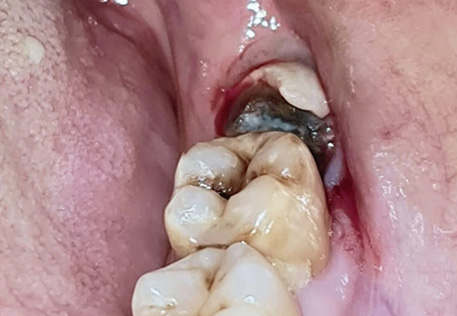

4. Tooth Decay – Partially erupted wisdom teeth are harder to clean, increasing the risk of cavities.

2. Infection – Bacteria can accumulate around a partially erupted wisdom tooth, leading to pericoronitis (gum infection).

3. Gum Inflammation – The gum tissue surrounding a wisdom tooth can become swollen and painful.